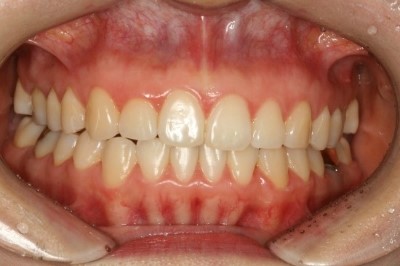

자, 다음은 정면에서 찍은 사진입니다

교정기간 : 6개월

가지런하게 정리가 되었네요~

윗니와 아랫니가 틀어짐 없이 깔끔하게 맞네요

이 환자의 경우 총 교정기간은 약 6개월 정도 소요되었습니다.